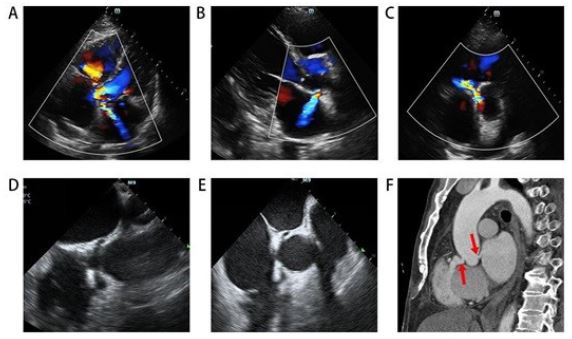

Four weeks later, the patient returned with chest pain, cough, and expectoration. Echocardiography, transesophageal echocardiography, and aortic CTA revealed two abnormal channels from the aortic sinus to the RV and LA (Figure 3). He was transferred to another hospital for cardiothoracic surgery, where surgeons confirmed the channels were caused by the knife stab (Figure 4).

Figure 3: Echocardiography (A-C). Trans esophageal echocardiography (D,E). Contrast-enhanced aortic CTA scan (F) showing two abnormal blood flows (arrows).